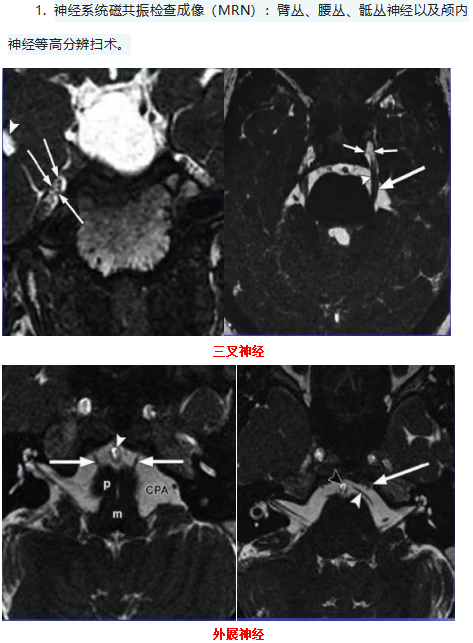

经过多年的磨合与探索,我们已经能够开展多种先进的检查,也能更好地满足医院医疗、教学、科研工作的需要。